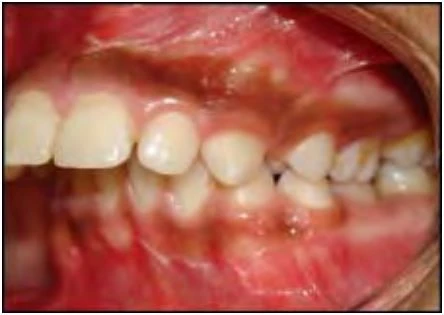

2.3 SAI KHỚP CẮN THEO MẶT PHẲNG NGANG

Trường hợp này bao gồm nhiều kiểu cắn chéo khác nhau. Thông thường các răng hàm trên nằm về phía ngoài so với các răng hàm dưới, nhưng đôi khi do cung răng hẹp hoặc vì một số lý do khác mà tương quan này bị xáo trộn. Chẳng hạn một hoặc nhiều răng hàm trên nằm về phía trong so với các răng hàm dưới, tình trạng này khác nhau về mức độ, vị trí và số lượng răng liên quan.